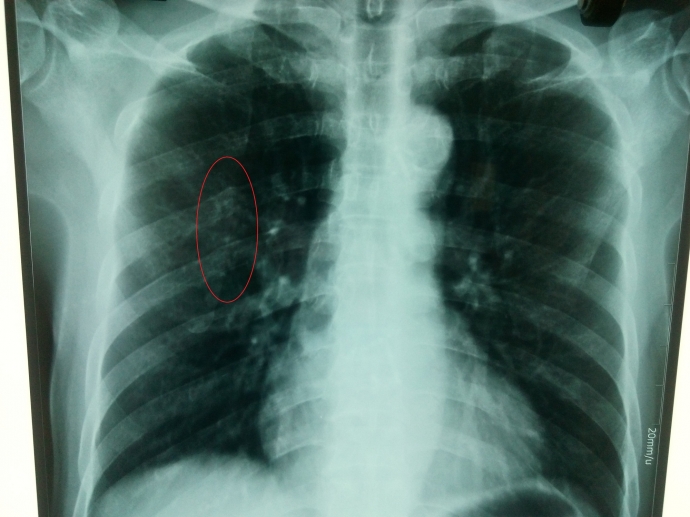

Phim X quang do BV quốc tế Vinh chụp ngày 24/3 và Bác sỹ Hường (BV quốc tế Vinh) chẩn đoán xương sườn bình thường (!?) |

PV đã liên hệ với Thạc sỹ Phan Thị Thu Hường, người được Trưởng khoa giới thiệu là “bác sỹ chẩn đoán hình ảnh giỏi nhất tỉnh Nghệ An”. Bác sỹ Hường khẳng định, “thực sự phim chụp X quang ngày 24/3 không có thấy rạn gãy xương”.

Tuy nhiên, trong vai người nhà bệnh nhân, PV đưa phim X quang của ông Hoàng do Bệnh viện quốc tế Vinh chụp sang bệnh viện khác nhờ đọc thì kết quả lại bất ngờ. Một vị bác sỹ cho biết, “với phim X quang này nếu để xem tim phổi thì tạm được, nhưng để xem xương thì kém. Chụp xem tim phổi khác, chụp xem xương phải khác. Do đó, trên phim này cũng khó xem xương, nhưng có điểm lưu ý ví dụ như cung sau xương sườn số 5”.

Dư luận đang đặt câu hỏi, liệu bác sỹ Hường do trình độ kém nên không nhìn thấy dấu vết nghi vấn trên cung sau xương sườn số 5, hay là bác sỹ Hường biết nhưng đã làm ngơ, không thông báo cho ông Hoàng biết (!?).